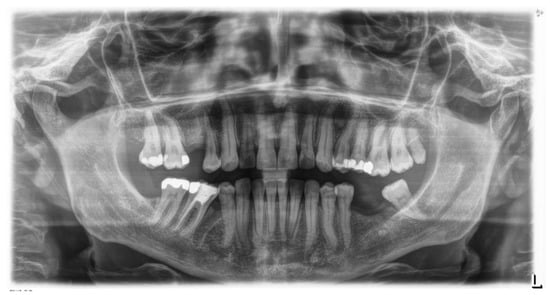

The patient is an 11-year-old female, in late mixed dentition. Clinical examination revealed acceptable oral hygiene, absence of functional anomalies and oral habits, the presence of deciduous molars (5.5 and 6.5), and erupting permanent teeth. The intraoral examination showed a molar and canine Angle class II on both sides, increased overjet, posterior unilateral functional crossbite on the right side, lower/upper midline deviated to the right/left of 2 mm, and increased overbite (5 mm) (Figure 6). The most important problem was that 1.3 was not in the arch, while the contralateral 2.3 had been present for more than 6 months. Diagnostic X-ray confirmed the 1.3 eruption delay. (Figure 7).

The 1.3 delayed eruption was probably due to the 1.4 mesial inclination and the absence of space. The patient, as demonstrated by cephalometric analysis and radiographic examination, was very near the growth peak, indicating the need to begin the treatment to obtain success of the orthodontic therapy.

Figure 7. Pre-treatment Orthopantomography.